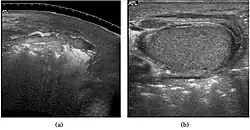

-

Fig. 29. Undescended testis. (a) Normal testis in the scrotum. (b) Atrophic and decreased echogenicity of the contralateral testis of the same patient seen in the inguinal region.